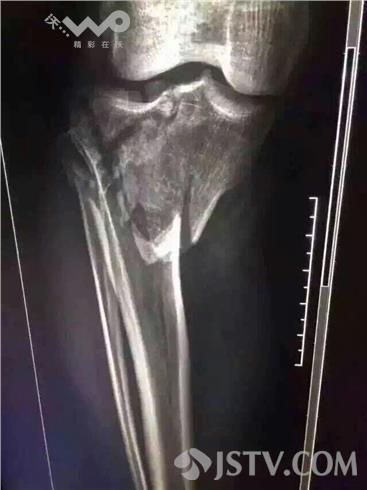

经诊断,医生被该男子殴打致右下肢胫腓骨骨折,目前已经入院治疗。据悉,涉事男子孙某为如皋本地人,目前已被警方控制,具体案情正在进一步调查中。